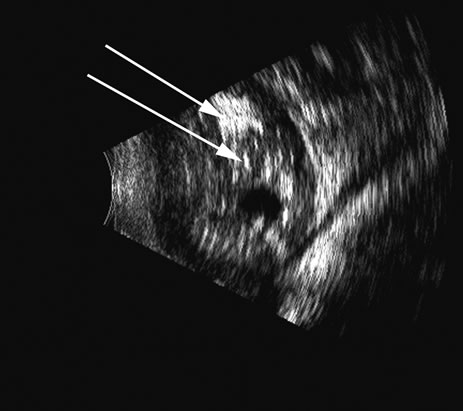

Hypotony is easily diagnosed by direct measurement of intraocular pressure, but the underlying cause is difficult to evaluate.11 High-frequency ultrasound scans can easily reveal separation of the ciliary body and the sclera. This allows different forms of hypotony to be determined—for example: tractional with membrane attached; primary as idiopathic, often inflammatory or hemorrhagic; and dehiscence secondary to iridodialysis or scleral perforation (Fig. 6).

Fig. 6. Hypotony of the eye generally is easily diagnosed by a separation of the ciliary body from the sclera. We have noted several types of such separation, such as tractional, primary (idiopathic), and dehiscence secondary to iridodialysis or scleral perforation, as in filtration procedures. In our series, greater than two clock hours of separation is typical of hypotony. The lower figure shows a concomitant thickening of the retina-choroid complex, also seen in hypotony (arrows). Long-standing hypotony typically has a shortened globe and possible retinal or choroidal separation.